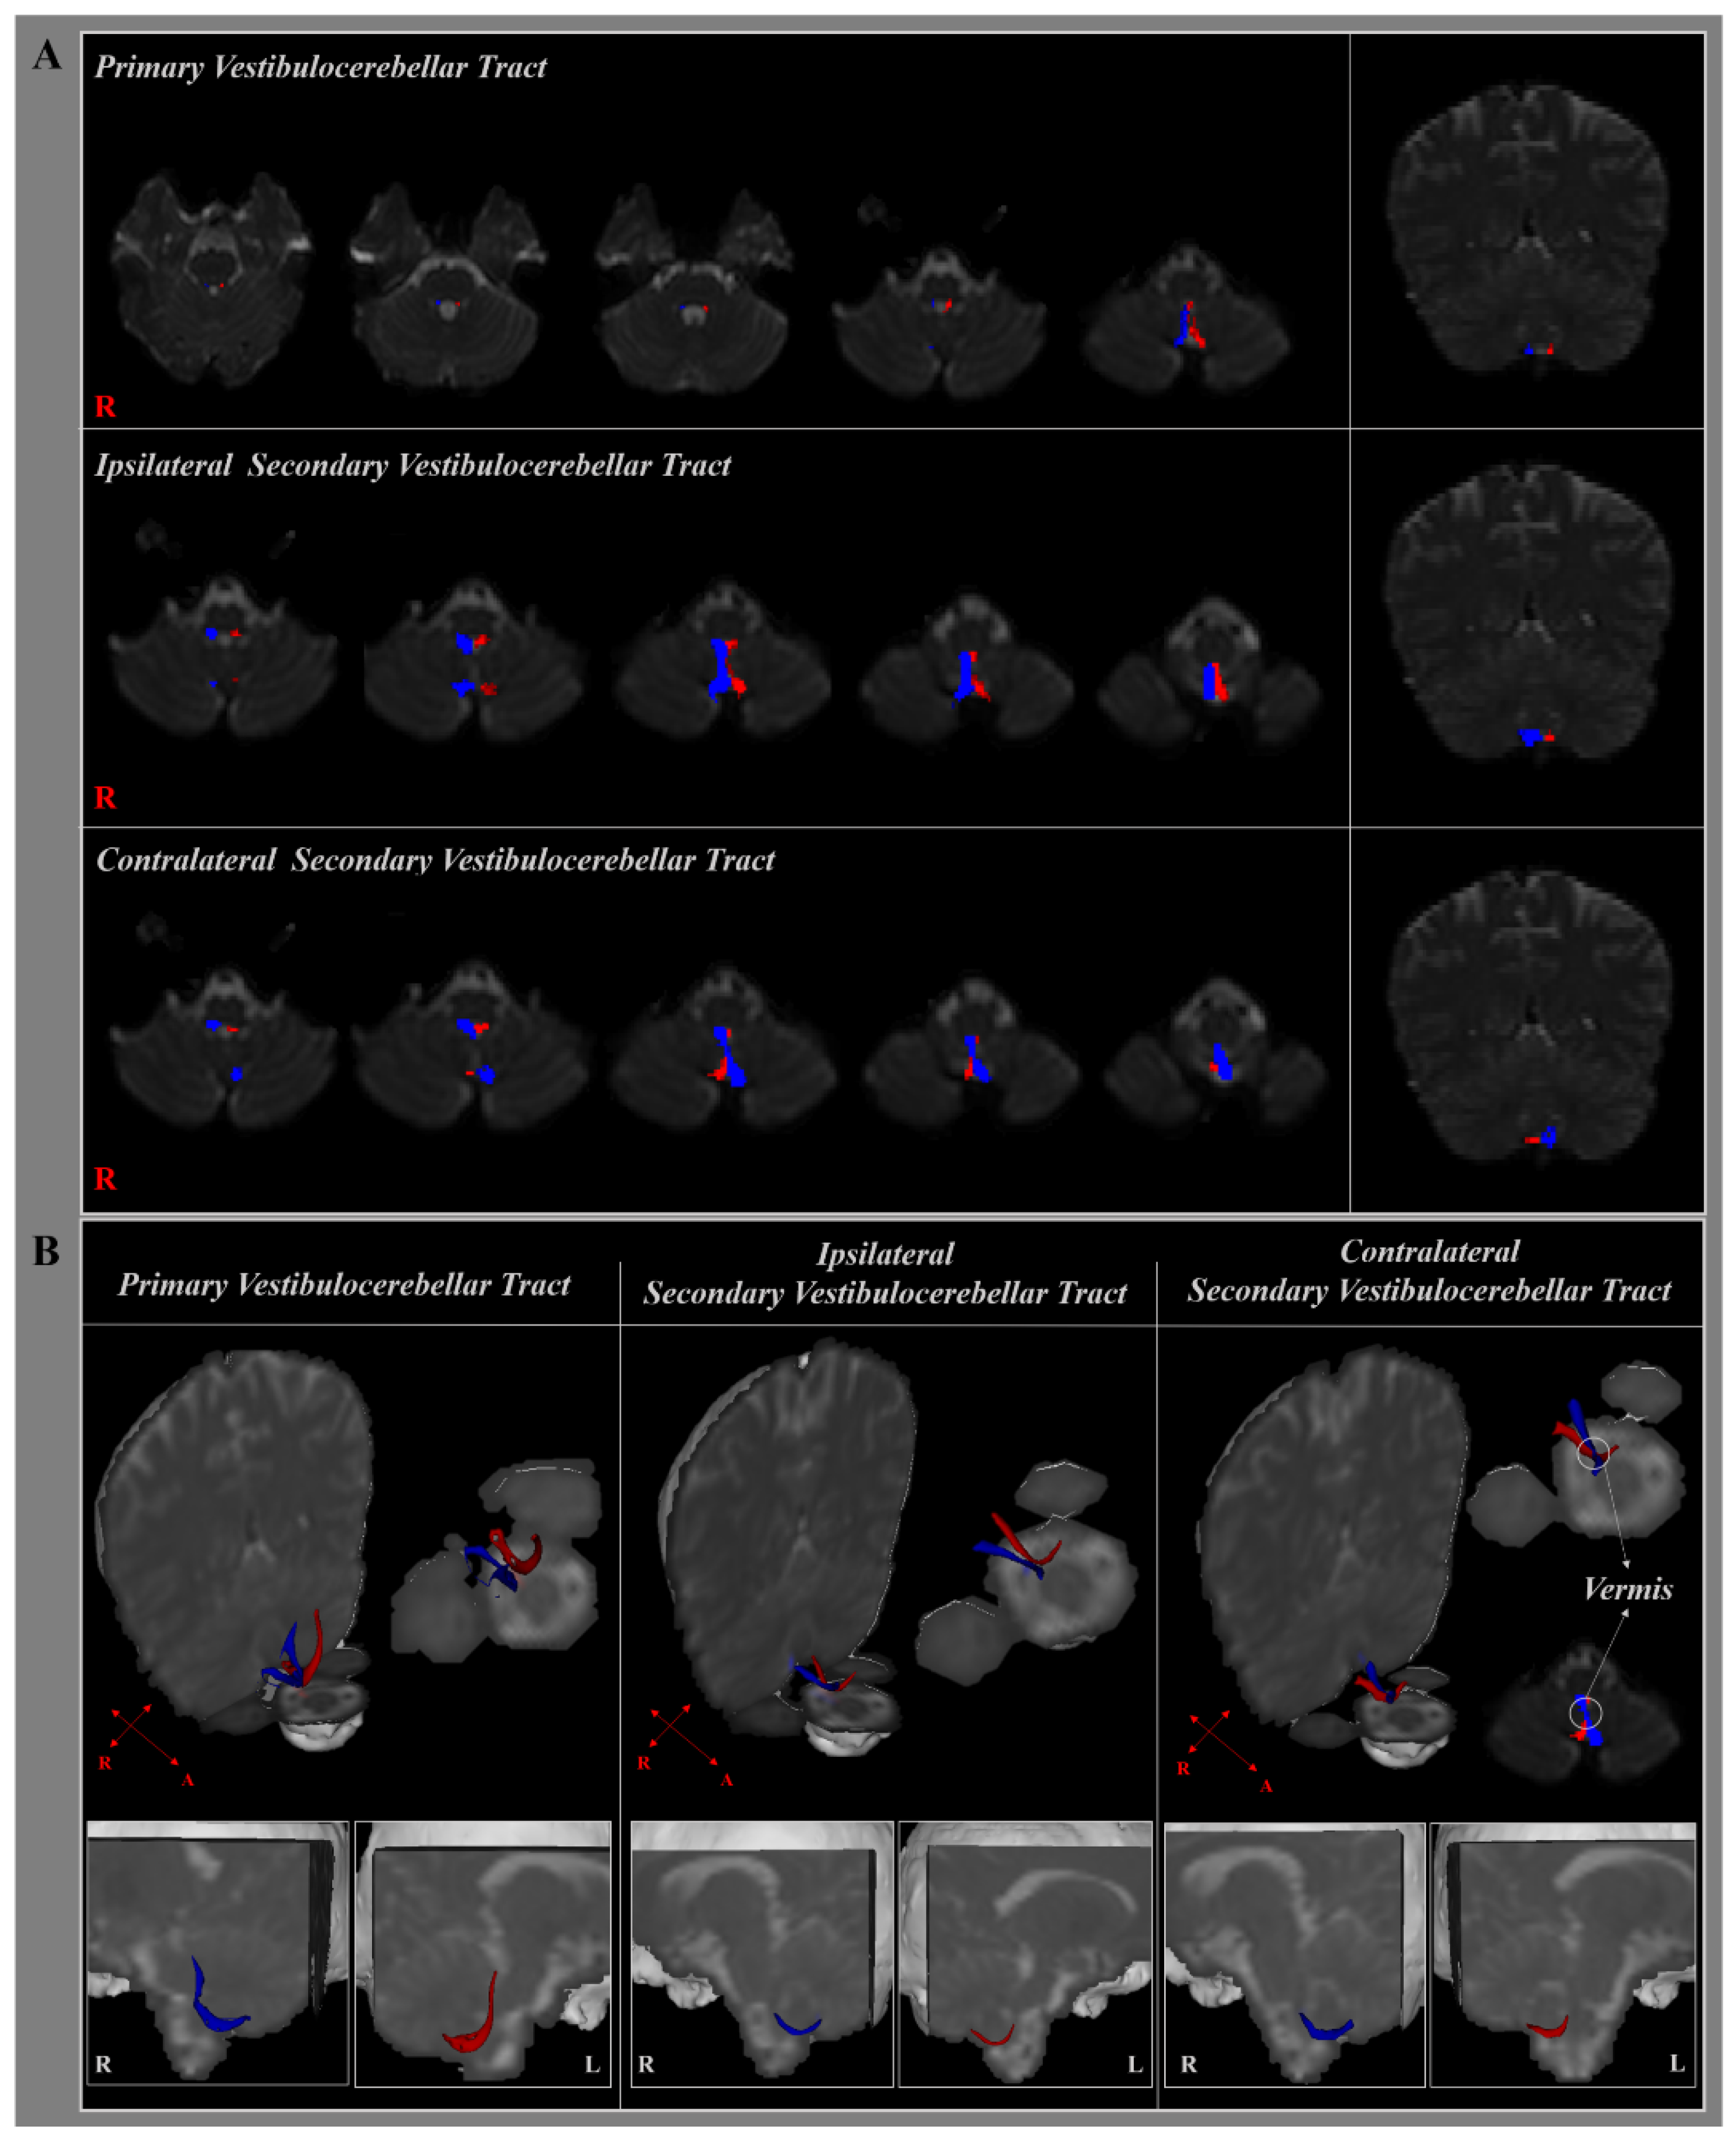

3. Results